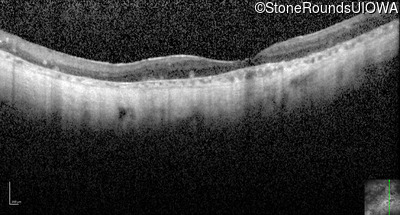

Optical Coherence Tomography - Left - Light Perception

Exemplar / OCT Stack